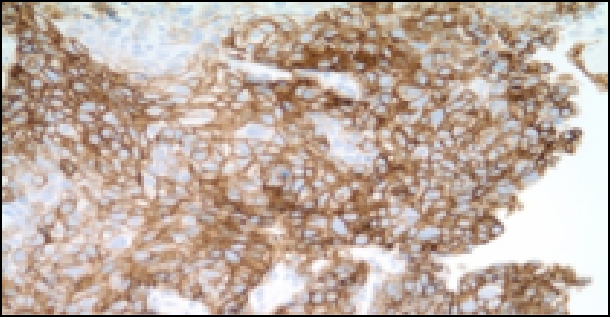

Az elvégzett immunhisztokémiai vizsgálatok EGFR, ALK, KRAS negativitás mellett PD-L1 90% pozitivitást mutattak.